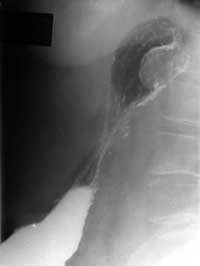

Cлучай лимфосаркомы желудка.

Рис. 2.  Боковая проекция. Дефект наполнения на задней стенке.